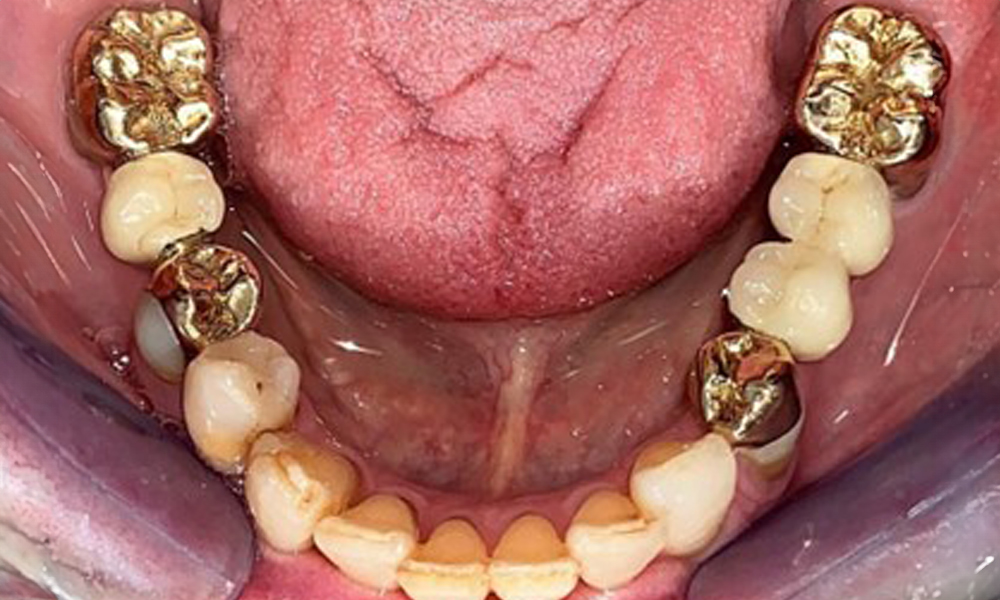

Die Patientin wurde vor über 25 Jahren mit einer kombinierten herausnehmbare Implantat-Teleskopprothese im Oberkiefer versorgt (Abb. 1, Abb. 2, Abb. 3) und ist sehr glücklich über ihren Zahnersatz. Im Unterkiefer hat die Patientin einen suffizienten festsitzenden Zahnersatz. (Abb. 4)

Dentaler Befund

Okklusalansicht Unterkiefer

Abb. 4: Okklusalansicht Unterkiefer